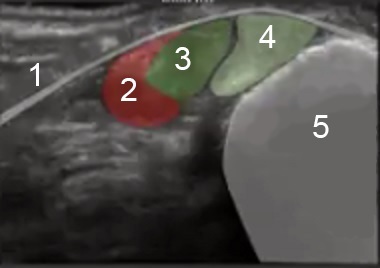

Bild 1: Fuß und Sprunggelenk, Peronealsehnen

1. Retinaculum patellae laterale

2. Muskelbauch

3. Peroneus longus

4. Peroneus brevis

5. Lateraler Malleolus der Fibula